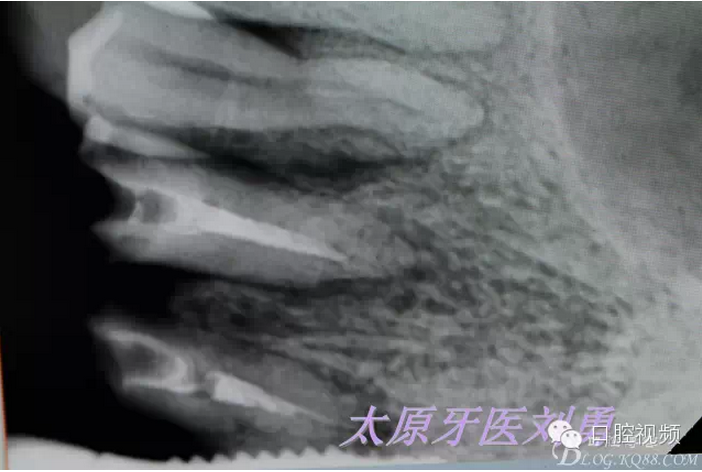

患者A1B1種植后連冠修復(fù)后6年。A23殘根,樁冠修復(fù)失敗,術(shù)前X片見根周陰影,牙根長度不佳,無法利用,建議患者即刻種植,并使用socket

shield技術(shù)。術(shù)前資料如下: